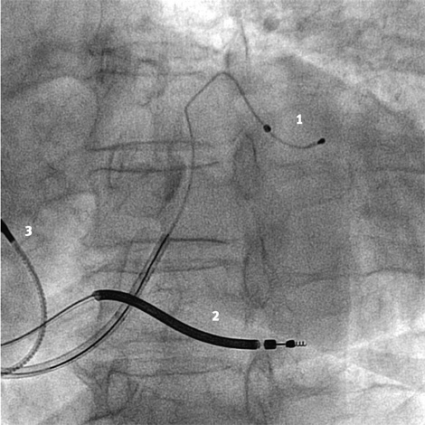

CRT-implantationen är ett tekniskt krävande ingrepp som för optimalt resultat kräver stor vana och bör förbehållas centra med stor volym. I dag görs ingreppet vanligen i lokalanestesi, och vänsterkammarelektroden placeras transvenöst. I vissa fall kan dock epikardiella elektroder placeras kirurgiskt genom en torakotomi. Vid en transvenös rutinprocedur kateteriseras sinus coronarius med hjälp av en speciell, lång införingshylsa. Ett venogram utförs med en ballongkateter för att kartlägga hjärtats venanatomi. En speciell pacingelektrod förs in i en epikardiell ven från vilken vänster kammare kan stimuleras. Det lämpligaste kärlet är oftast sinus coronarius posterolaterala gren. Stimuleringsläget väljs rutinmässigt inte utifrån hemodynamisk effekt utan beroende på de tekniska pacingparametrarna sensing- och tröskelvärde.